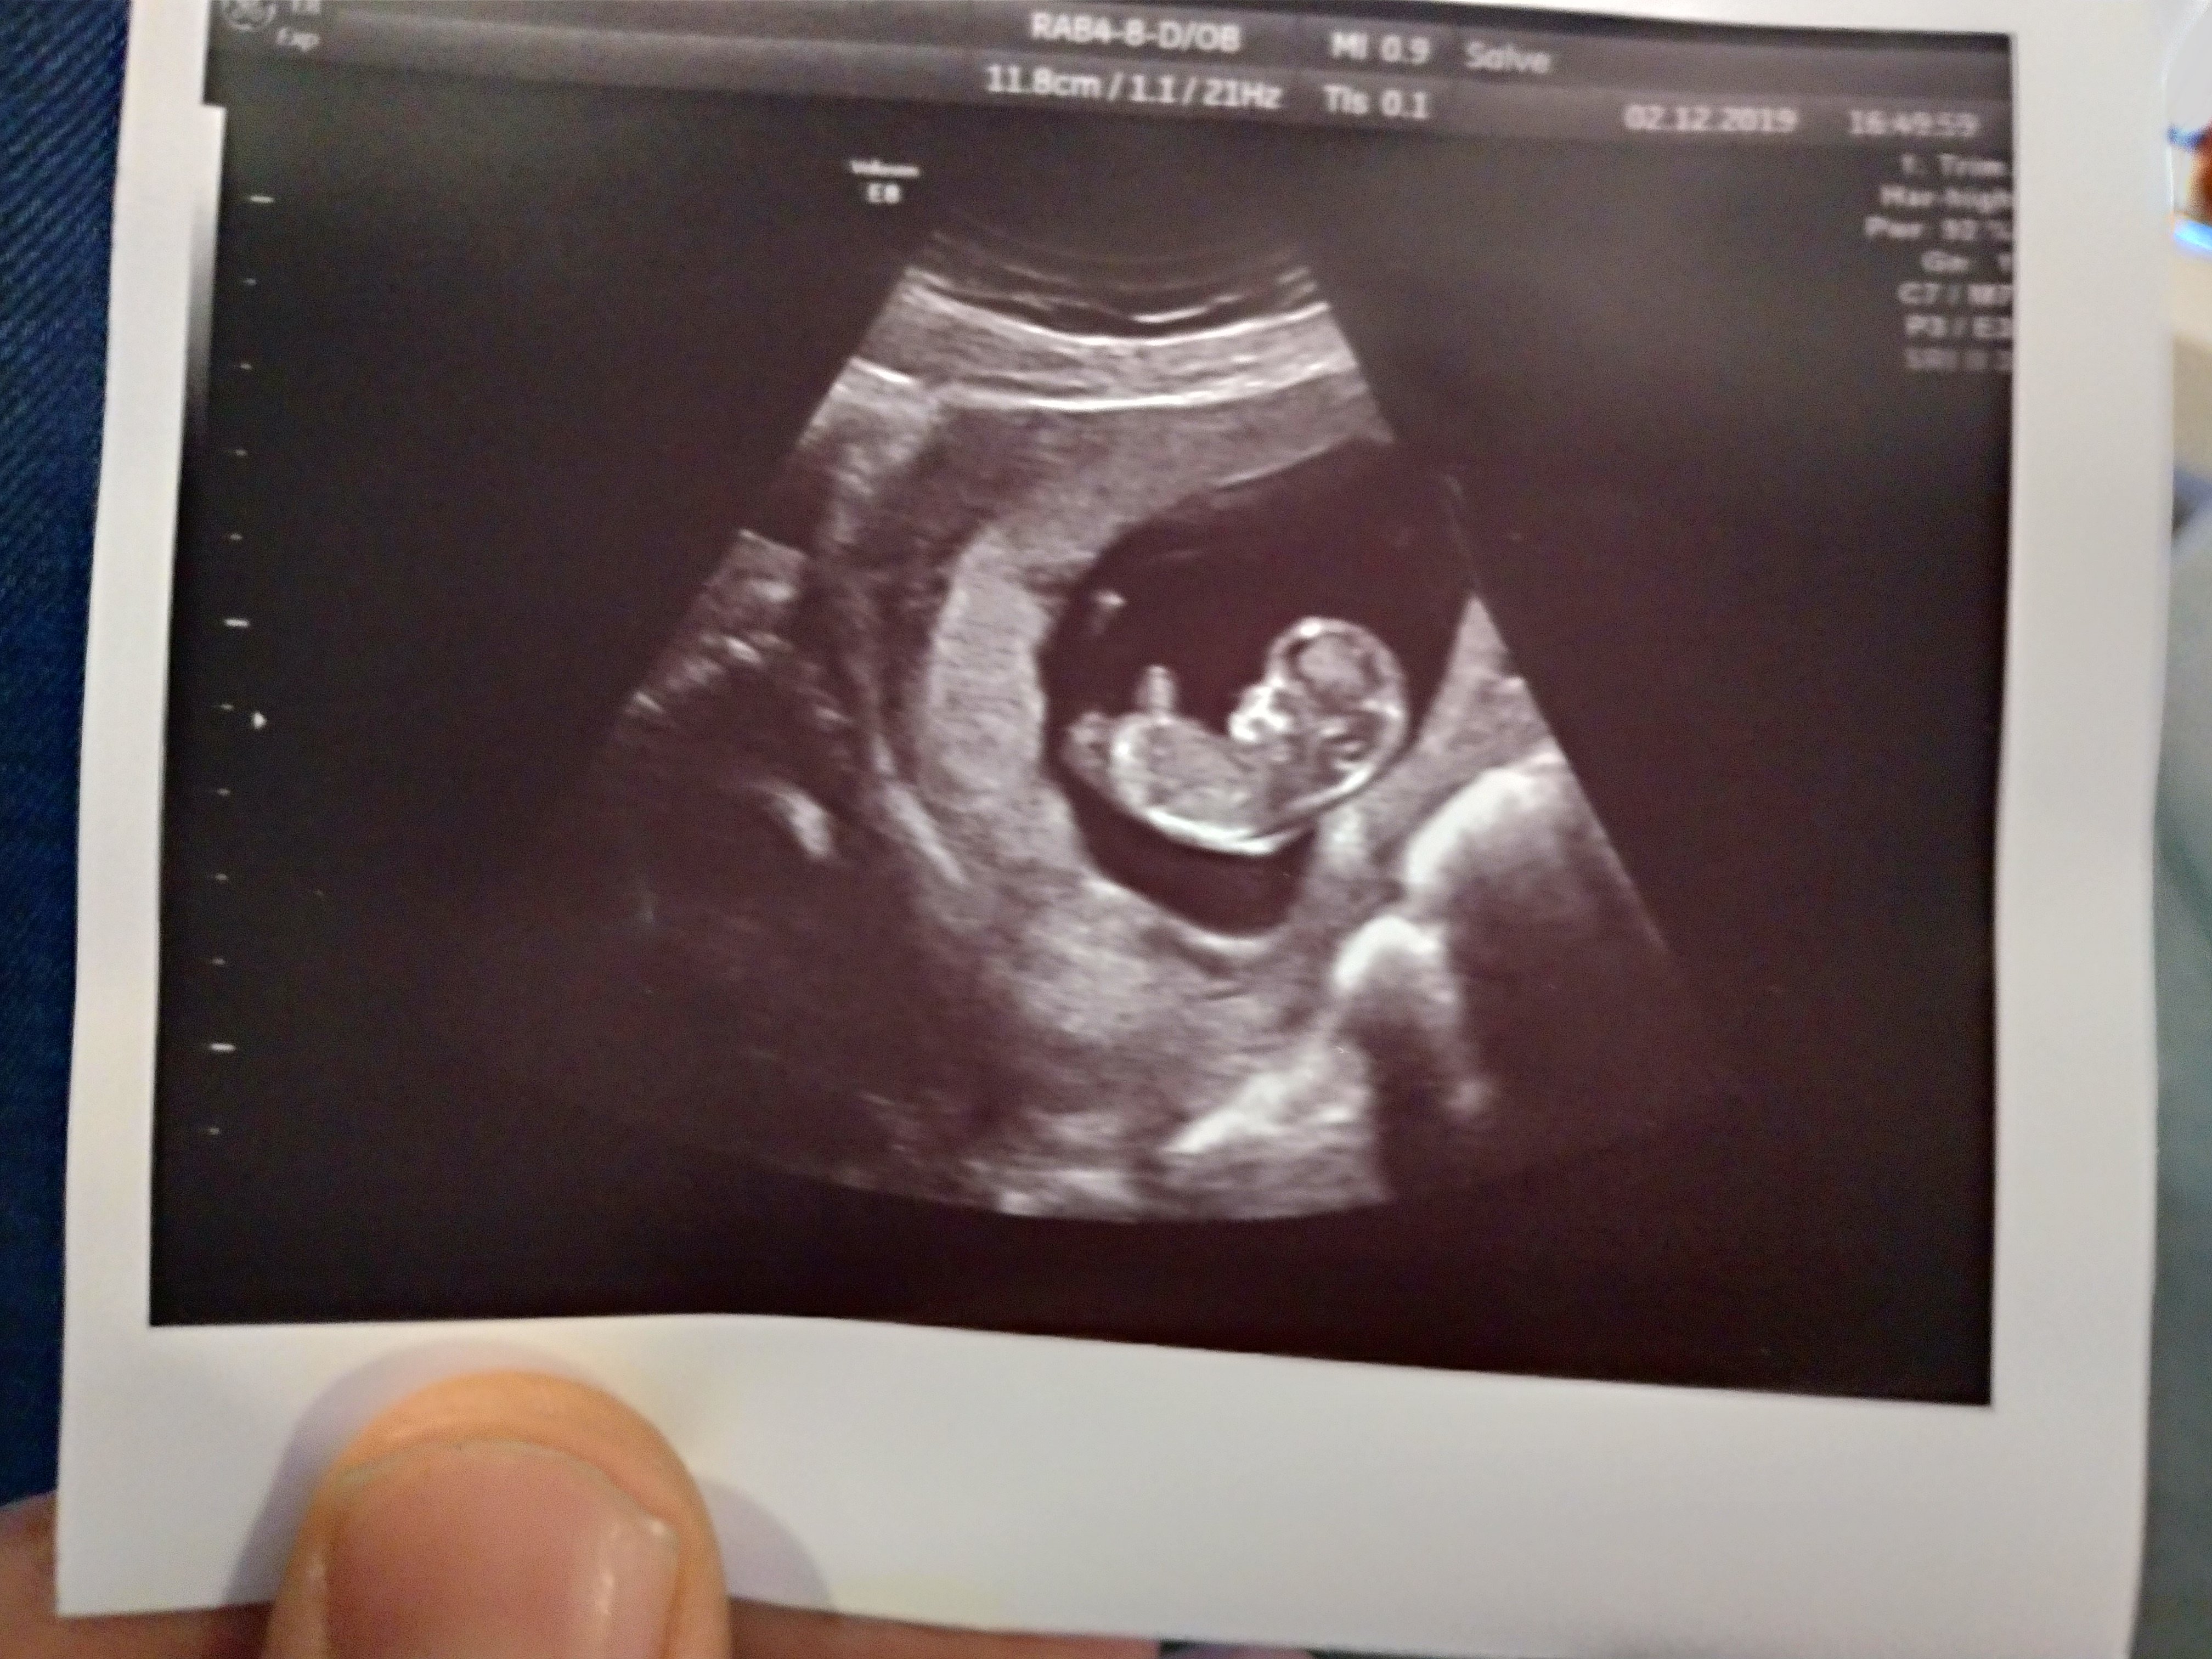

11 tydzień i w końcu USG. Martwi mnie to, że jest 11,8 cm, czy to nie o wiele za dużo jak na 11 tydzień ciąży? :o

Załączniki

• P_20191202_183338_vHDR_Auto_HP.jpg

P_20191202_183338_vHDR_Auto_HP.jpg

1,8 MB · Wyświetleń: 162